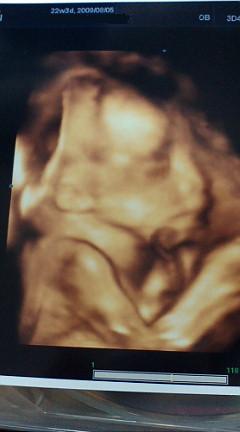

と、今日は自論を熱く語ってしまいましたが・・・6ヶ月健診のベイビーを貼っておきます!

4Dなのでリアルでしょ?

ただいま616gです。大きくなったなあ。